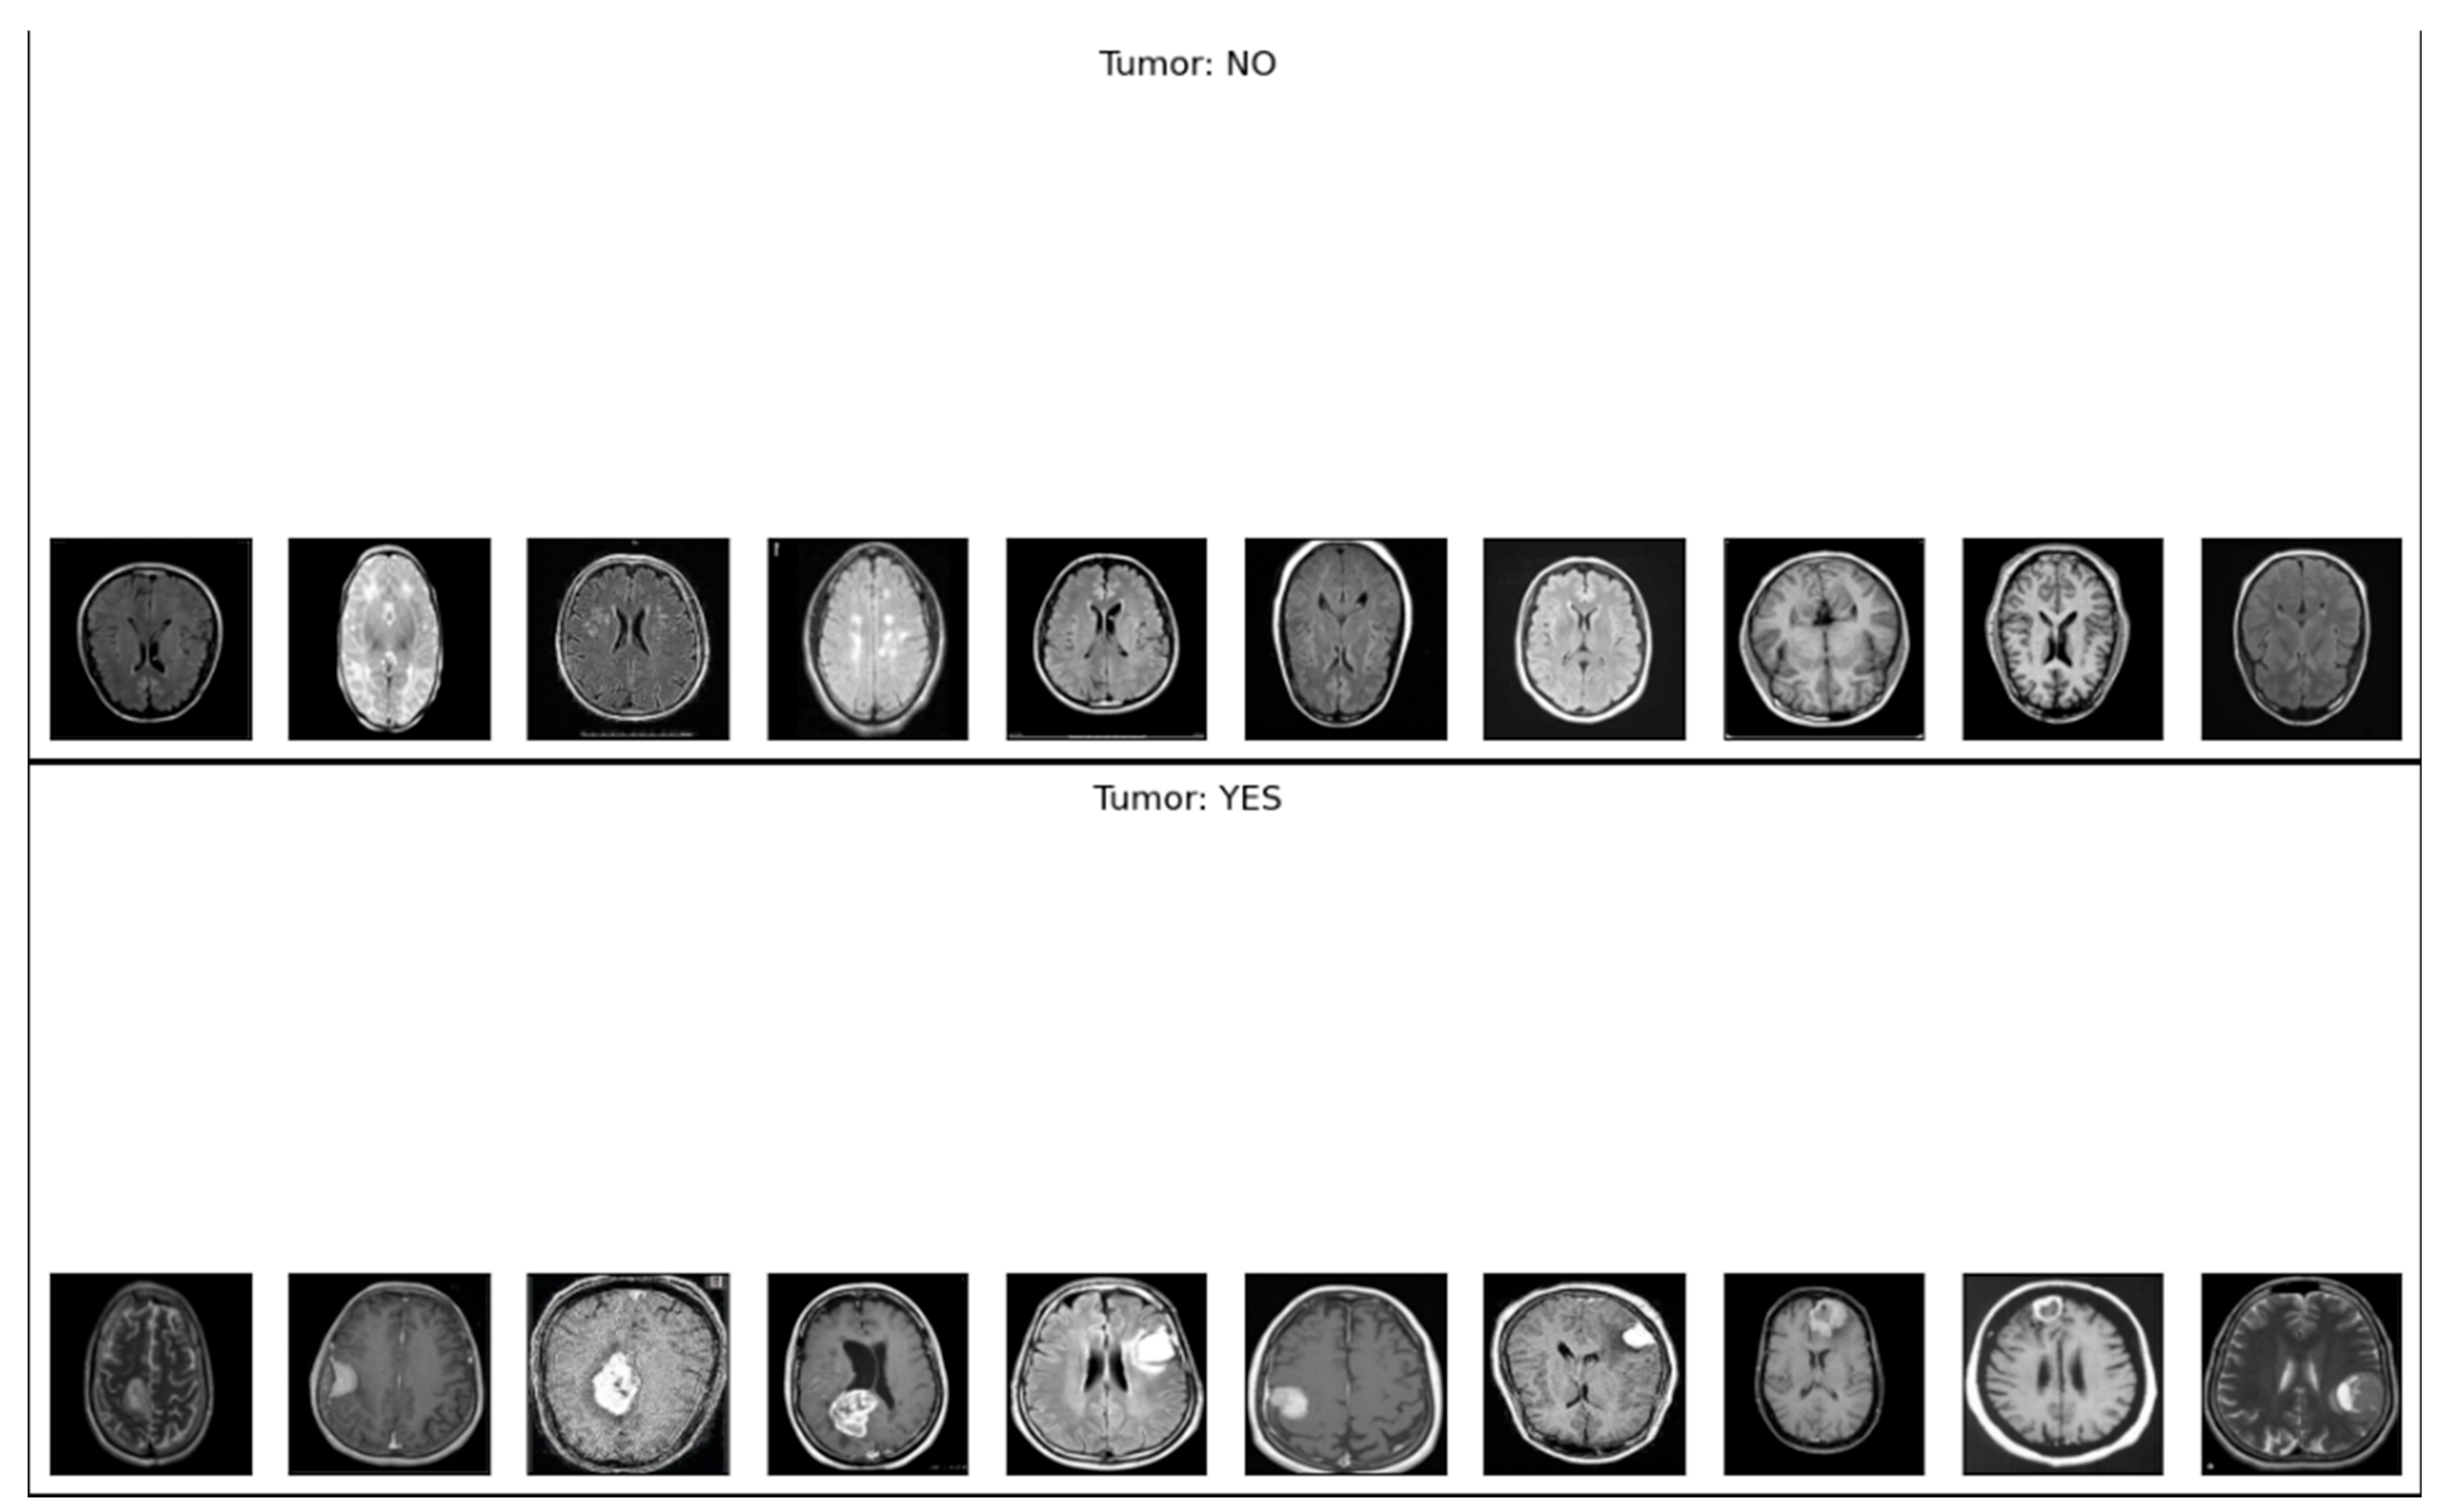

The EfficientNetB4 model demonstrated outstanding performance, achieving an F1-score of 100% on the test set. Out of 300 test images, only one instance was misclassified, indicating exceptionally high precision and recall. Figure 12 presents a sample prediction output of the model, further illustrating its strong capability in distinguishing between tumor and non-tumor MRI images.

This section presents a comparative analysis of the deep learning models evaluated in this study, namely CNN, VGG16, and EfficientNetB4. As shown in the Classification Report Heatmap in Figure 13, the EfficientNetB4 model achieved perfect performance, obtaining precision, recall, and F1-score values of 1.00 for both tumor (YES) and non-tumor (NO) categories using 999 test samples. These results indicate that the model correctly classified all instances without any misclassifications, demonstrating 100% classification accuracy.

The superior performance of EfficientNetB4 highlights the effectiveness of its compound scaling strategy and advanced feature extraction capabilities, proving its advantage over traditional CNN and VGG16 architectures in MRI-based brain tumor detection. The Confusion Matrix presented in Figure 14 provides a visual representation of the model’s classification performance. Out of 400 test samples, only two instances were misclassified—one as a false positive and one as a false negative—resulting in an impressive overall accuracy of 99.5%. The strong diagonal dominance within the matrix highlights the model’s high discriminative capability and its ability to accurately distinguish between tumor and non-tumor MRI scans.